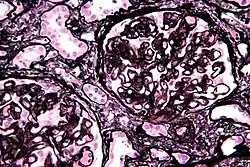

Micrograph of membranous nephropathy showing prominent glomerular basement membrane spikes. Jones' stain.

The defining point of MGN is the presence of subepithelial immunoglobulin-containing deposits along the glomerular basement membrane (GBM).

• By light microscopy, the basement membrane is observed to be diffusely thickened. Using Jones' stain, the GBM appears to have a "spiked" or "holey" appearance.

• On electron microscopy, subepithelial deposits that nestle against the glomerular basement membrane seems to be the cause of the thickening. Also, the podocytes lose their foot processes. As the disease progresses, the deposits will eventually be cleared, leaving cavities in the basement membrane. These cavities will later be filled with basement membrane-like material, and if the disease continues even further, the glomeruli will become sclerosed and finally hyalinized.

• Immunofluorescence microscopy will reveal typical granular deposition of immunoglobulins and complement along the basement membrane.[16]